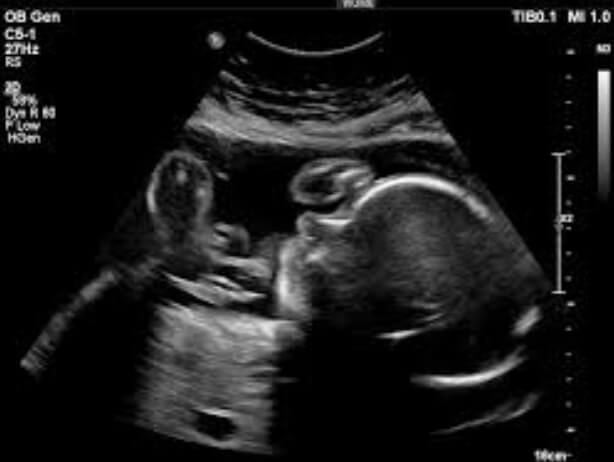

26 Haftalık Bebeğin Ultrason Görüntüsü

Bebeğinizin ultrasondaki görüntüsünün internette karşınıza çıkan herhangi bir fotoğraftan çok farklı olması dahi sizi şaşırtmamalıdır; çünkü her bebeğin anne karnındaki duruş ve hareket alışkanlıkları farklıdır. Ayrıca bebeğinizin o anki konumuna bağlı olarak da görüntüde değişim olması normaldir. Genel hatlarıyla bakarsak ise;

• Ultrasonda bebeğinizin yüzünü ayrıntılı görebiliyorsanız, 26 hafta gebelik sürecinde bebekte yüzün tüm organlarını rahatlıkla seçebilirsiniz; çünkü hepsi 25. haftanın sonu ile fiziksel gelişimini tamamlamış bulunmaktadır. Yalnızca göz kapaklarının açılması için bu haftanın da tamamlanması gerekmektedir.

• Bebeğinizin hareket kabiliyetinin oldukça arttığı, ancak anne karnındaki alanın da henüz ona dar gelmeye başlamadığı bu şanslı haftalarda, siz hissetmiyor dahi olsanız bebeğiniz çok hareketlidir. Bu hareketliliği ultrasondaki duruşundan, ellerini sıkıyor oluşundan, ayaklarına uzanışından hatta göbek kordonunu tutuşundan anlayabilirsiniz.